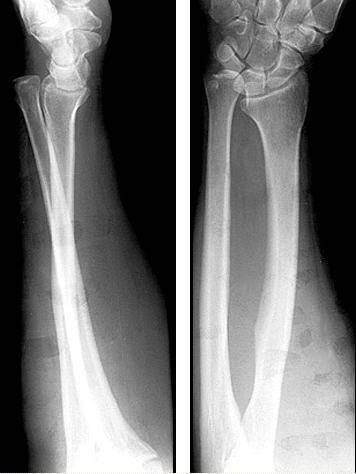

Galeazzi骨折

盖氏骨折:桡骨干骨折伴下尺桡关节脱位。